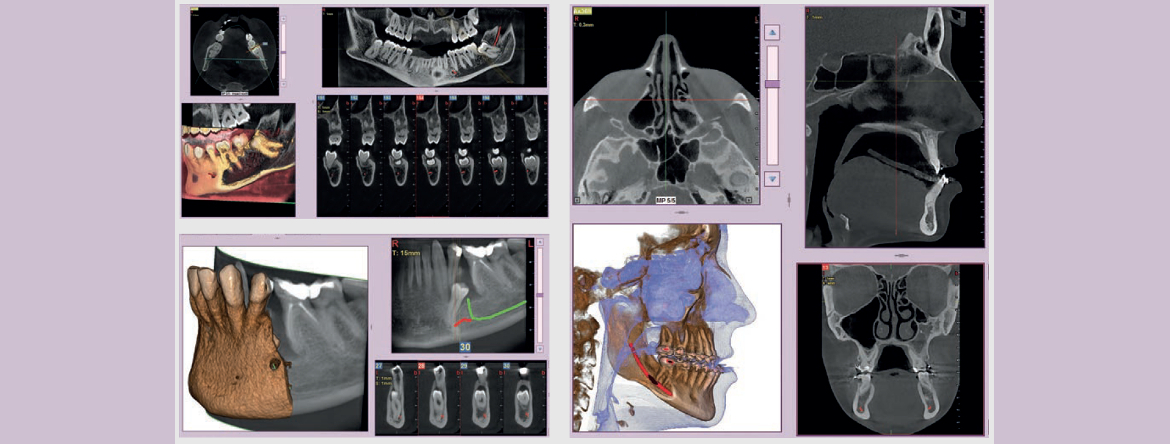

• O que é necessário para as radiografias intraorais, Ortopantomografias e CBCT.